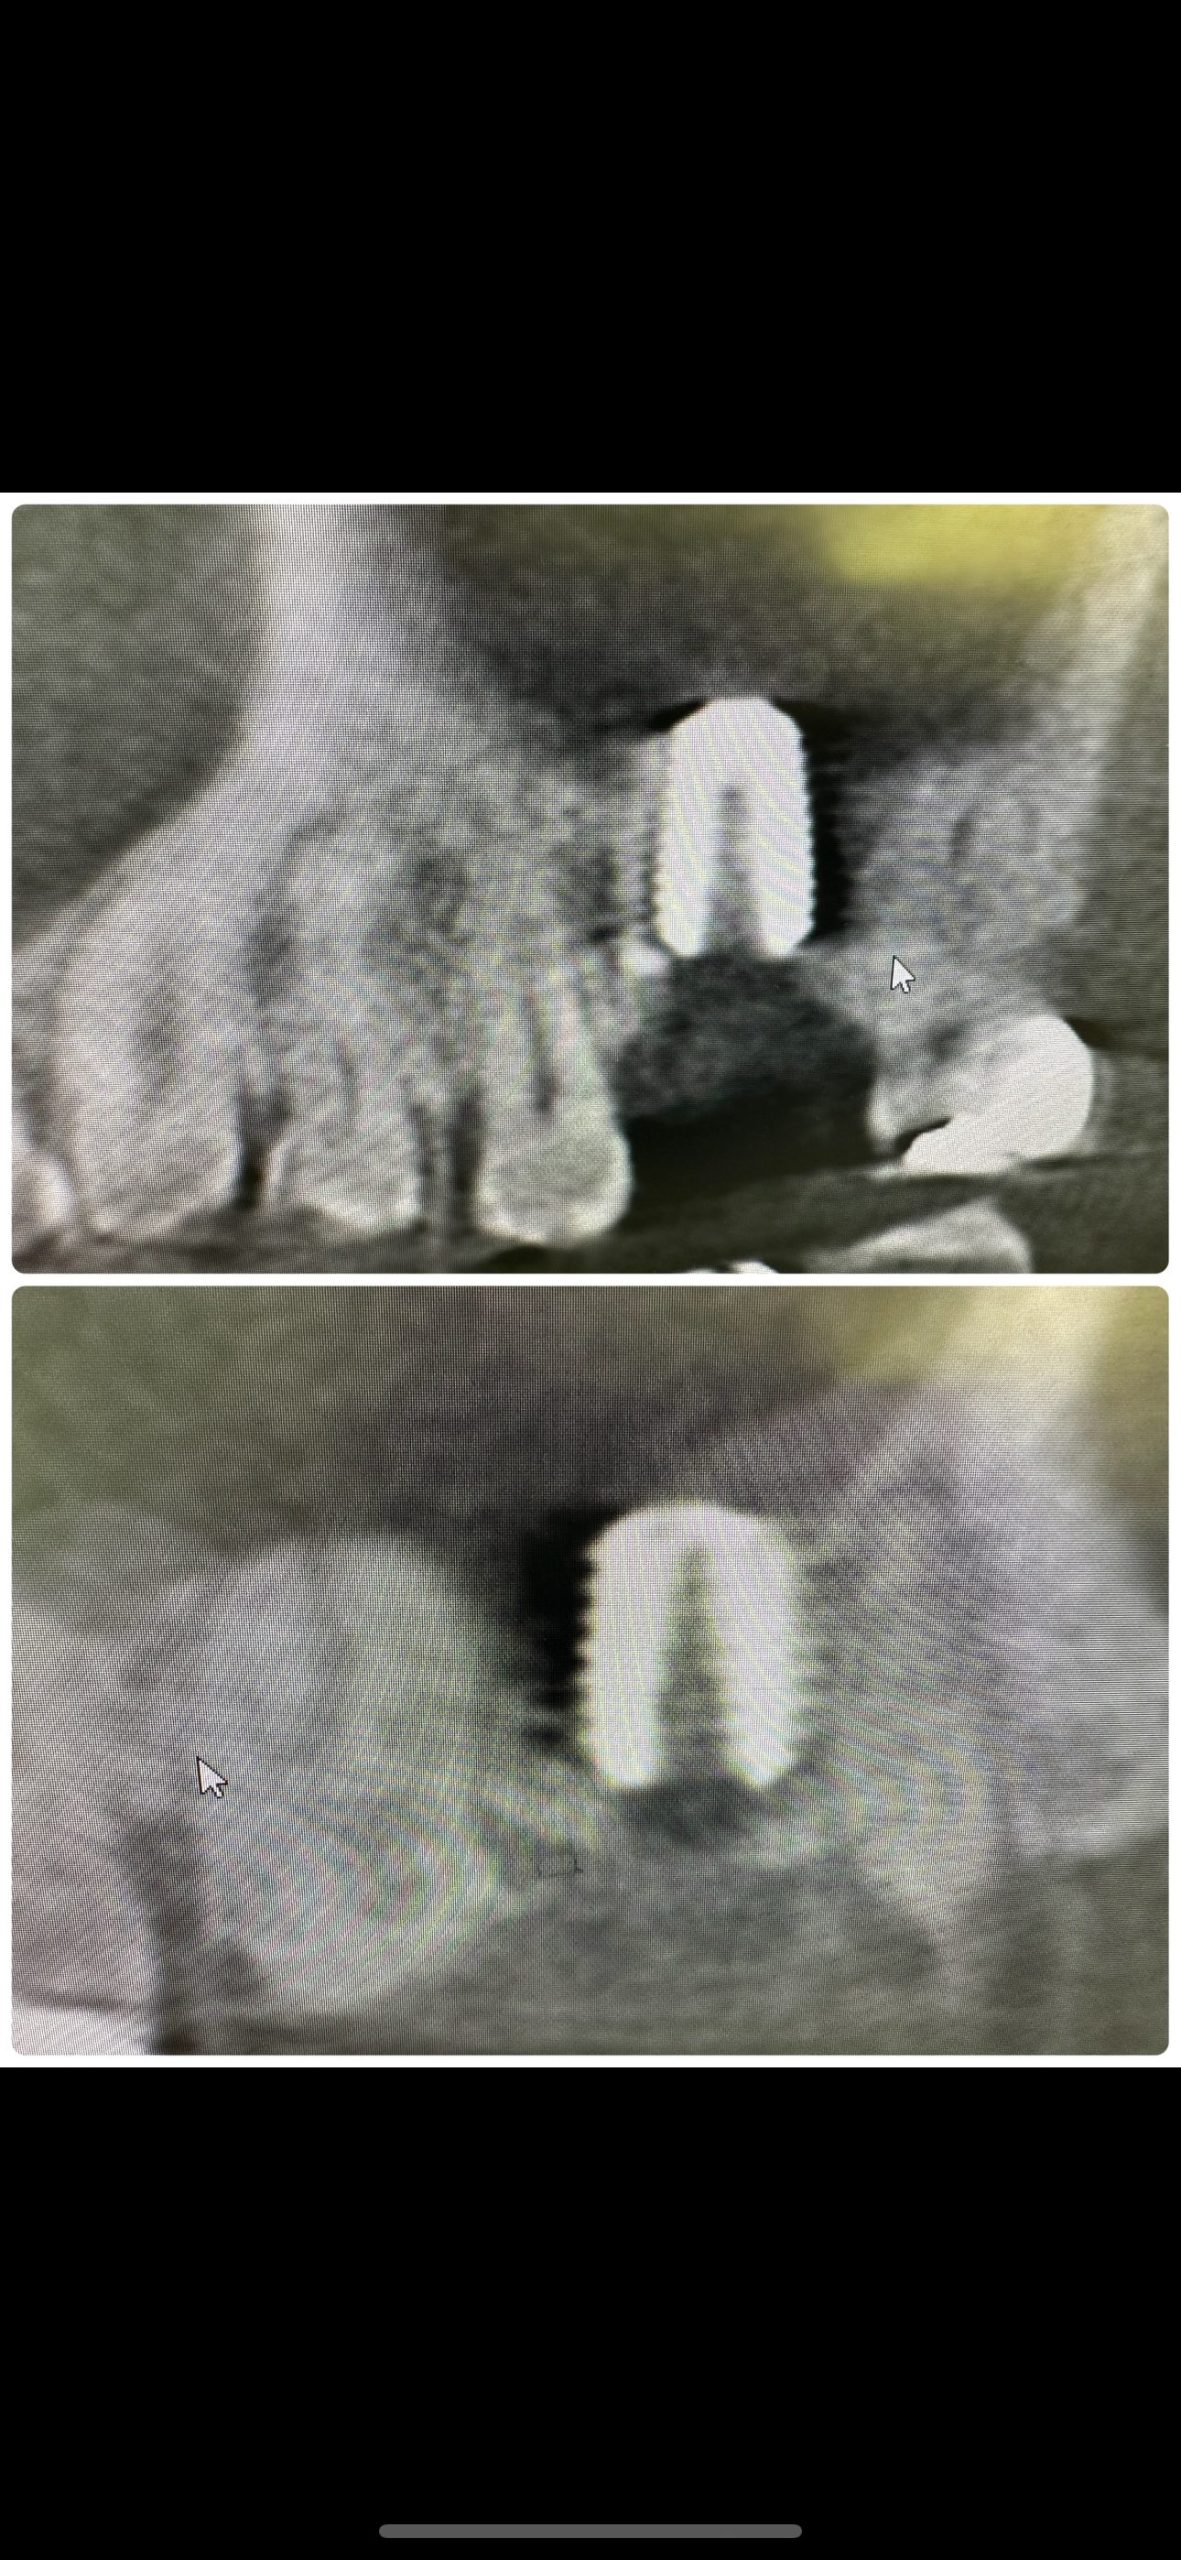

新大久保歯科医院